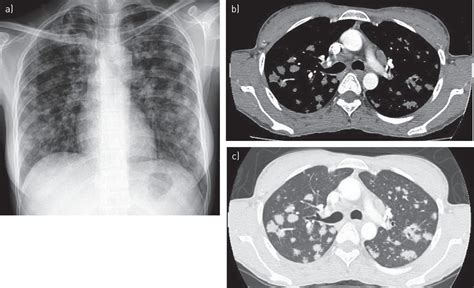

Miliary Nodularity in a Patient Receiving TNF Inhibitors ... from www.jrheum.org Find out if this is available in your part of the world. However, it can occur in other heart and lung diseases. Indeed, a differential diagnosis during this time may include malignancy, tuberculosis, sarcoidosis, and other pulmonary infections or fungal diseases such as histoplasmosis. The delay in the diagnosis of lung cancer is substantial, because new malignant lesions can be obscured by coexisting tuberculosis lesions, or new nodules could be hidden by active tuberculosis lesions or might be incorrectly interpreted as an increase in severity of tuberculosis. Endobroncheal tuberculosis is defined as tuberculous infection of the tracheobronchial tree with microbial and histopathological evidence. Differentiation according to the radiological findings can not be provided. Both conditions affect the lungs, but they have different pathology. Tuberculosis may increase lung cancer risk through substantial and prolonged pulmonary inflammation.